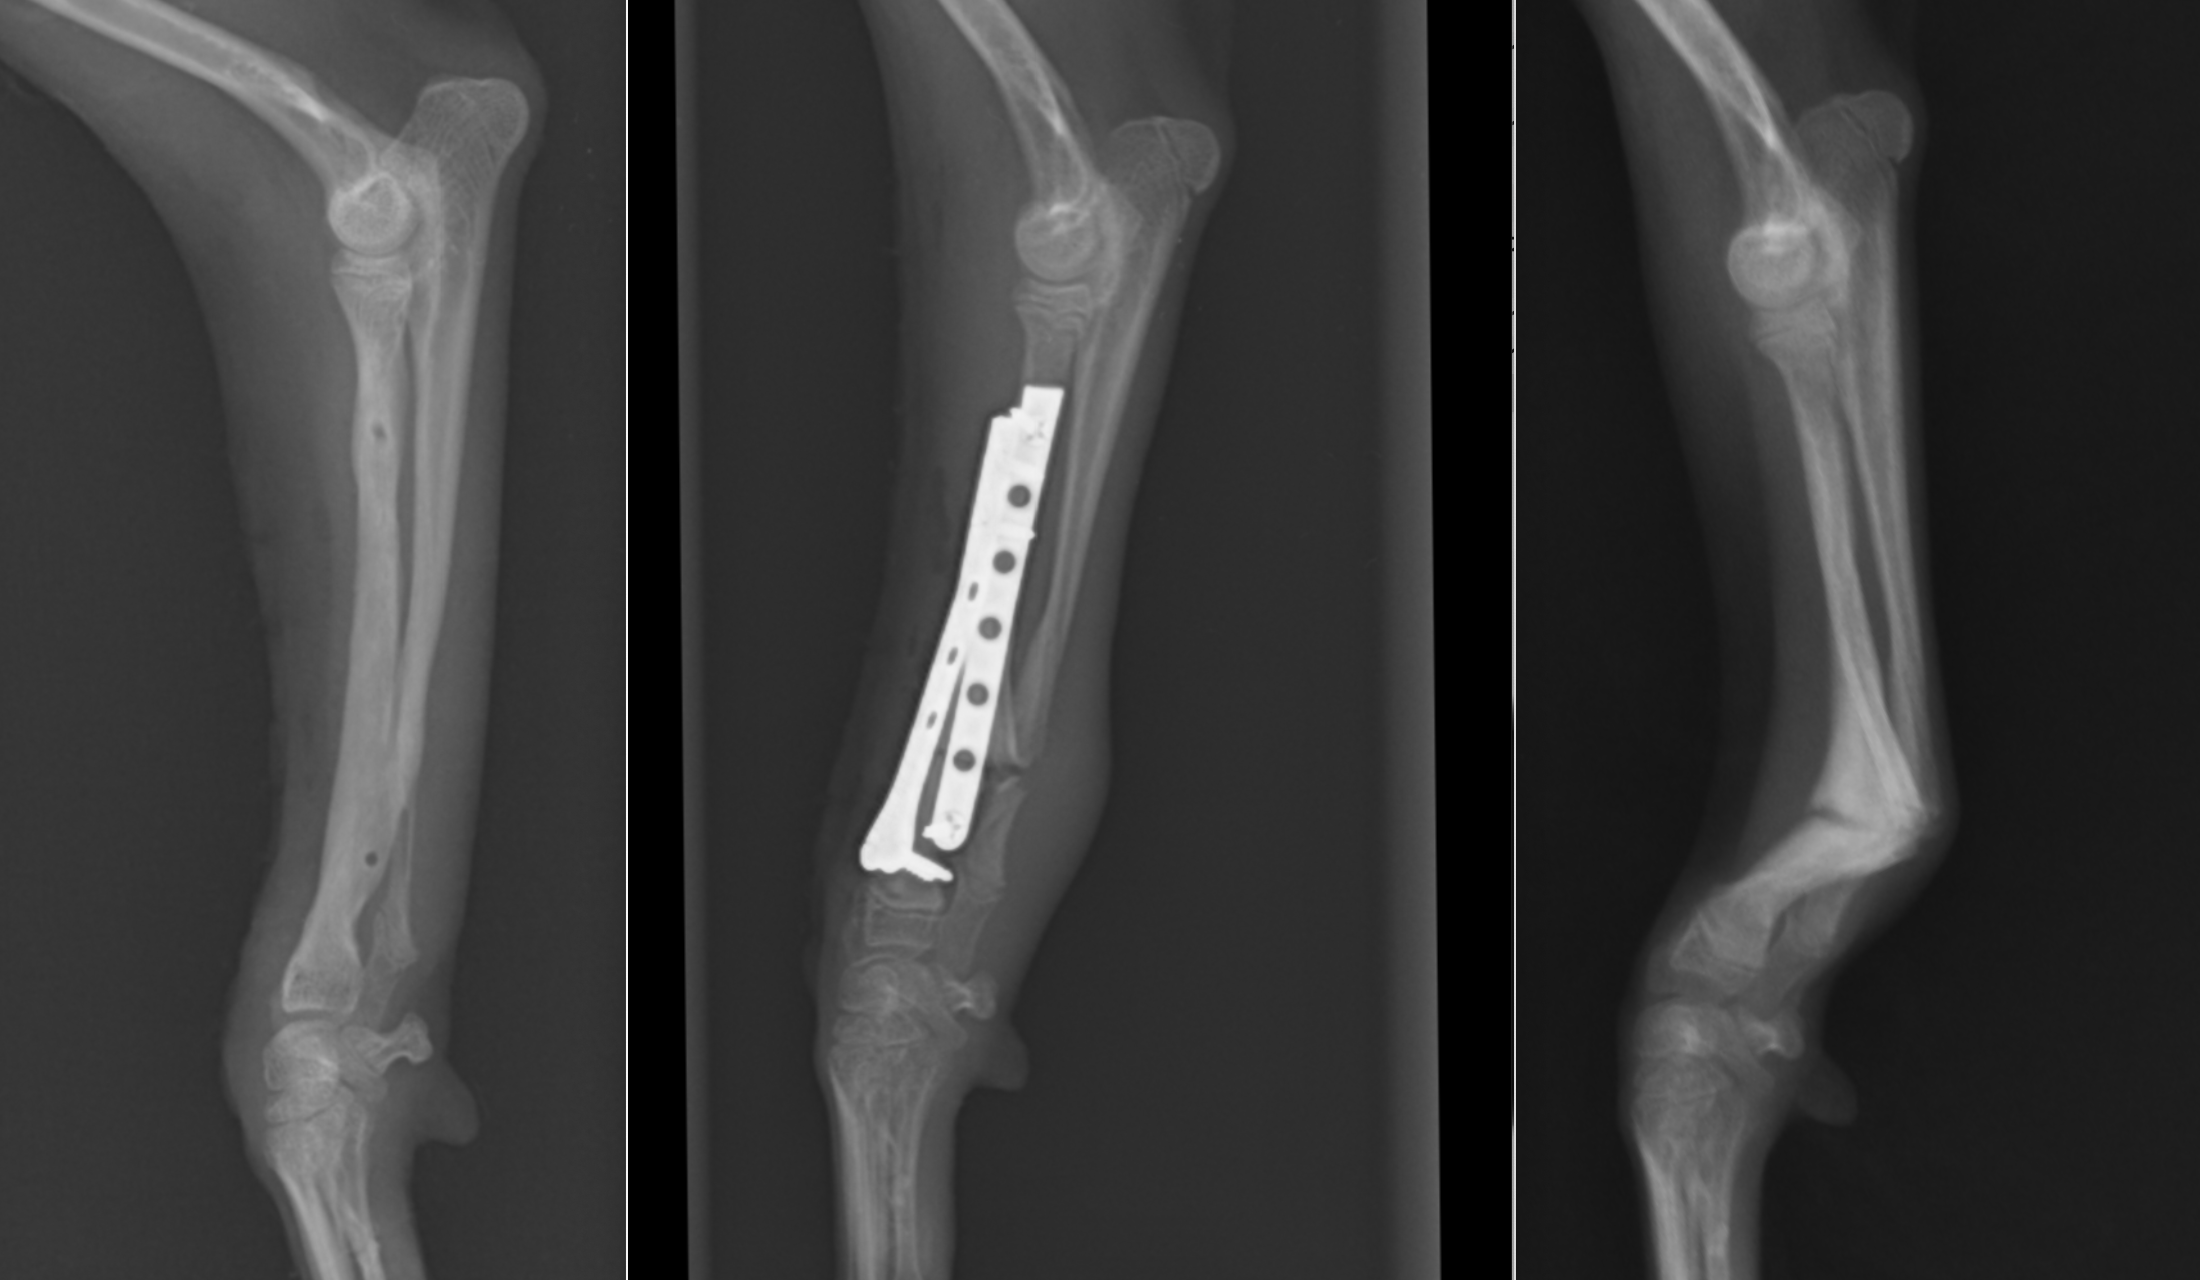

2025年6月22日開催の第110回日本獣医麻酔外科学会学術集会にて磯野がパテラ(膝蓋骨内方脱臼)の形態学的変化についての発表を行いました。CT画像をもとに脛骨の形態学的変化についてご説明させていただきました。

整形外科の雑誌であるVeterinary and Comparative Orthopaedics and Traumatologyに磯野の論文である「Tibial Torsion Malalignment in Small Dogs with Medial Patellar Luxation」が掲載されました。パテラ内方脱臼に対し、脛骨粗面と足根骨の捩れが関与しているをことを示し、その指標の一つを提言した内容になります。ご興味ある方はご覧ください。